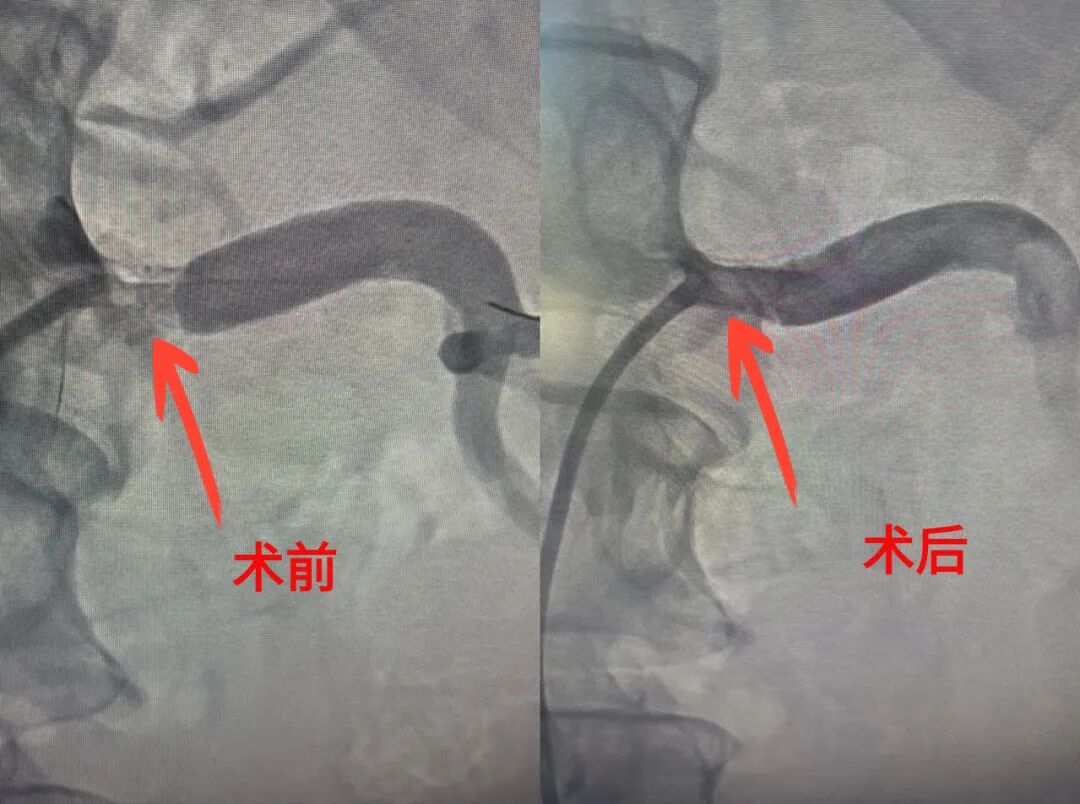

肾动脉狭窄支架植入术:守护肾脏“生命线”

针对肾动脉狭窄这一影响肾脏功能及全身健康的严重疾病,中心迅速响应,精准施策。通过肾动脉狭窄支架植入术,不仅有效拓宽了狭窄的血管腔,恢复了肾脏的正常血流,还极大地降低了高血压及相关并发症的风险,为患者的生活质量提供了坚实保障。